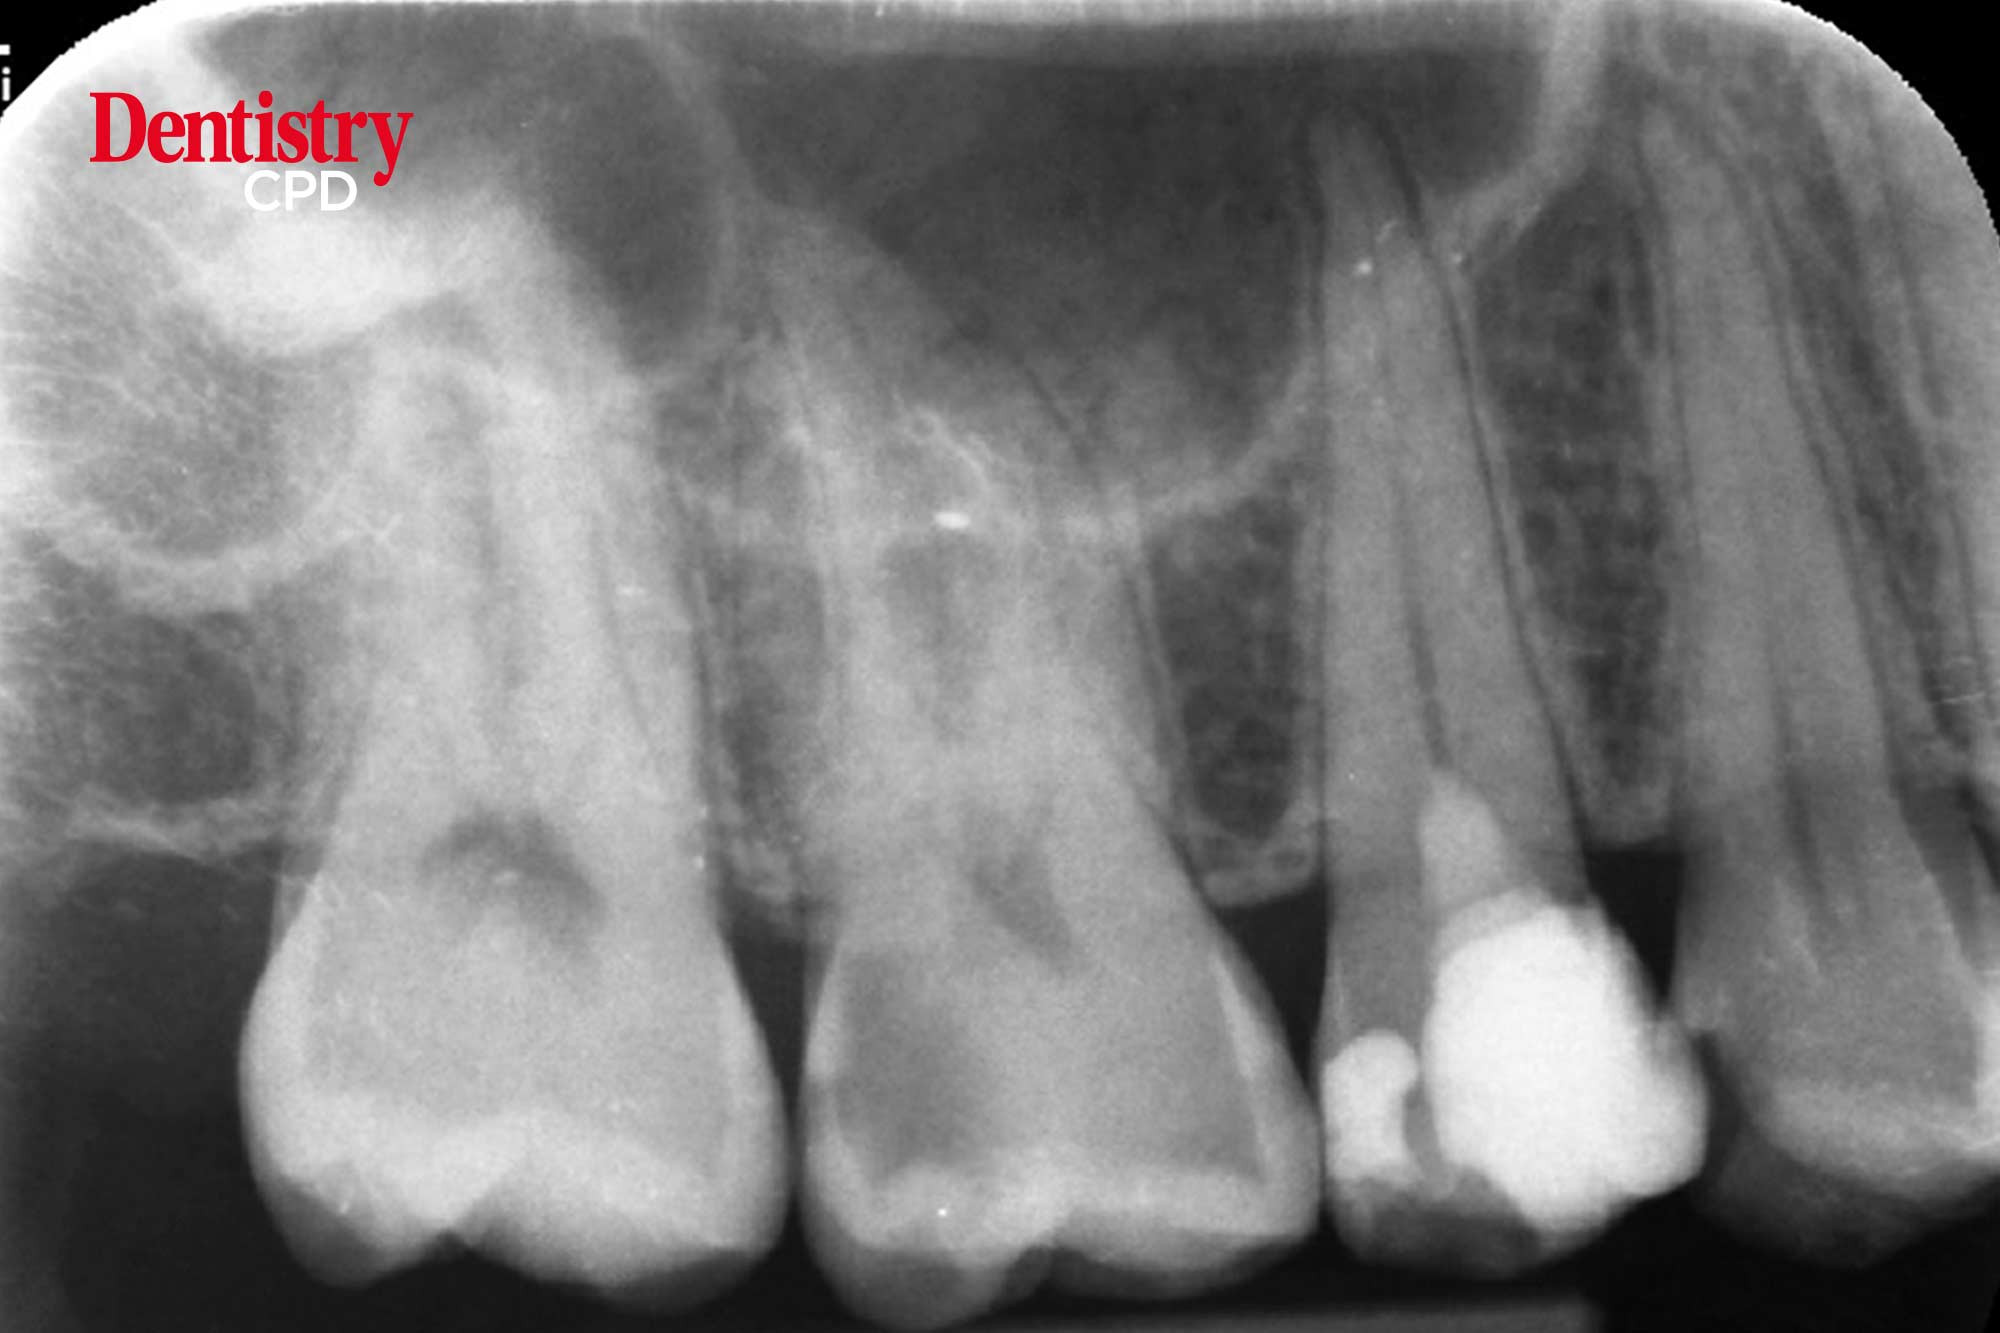

Awaz Sharief discusses the use of pulpotomy to treat irreversible pulpitis.

To discuss the use of pulpotomy to treat irreversible pulpitis.